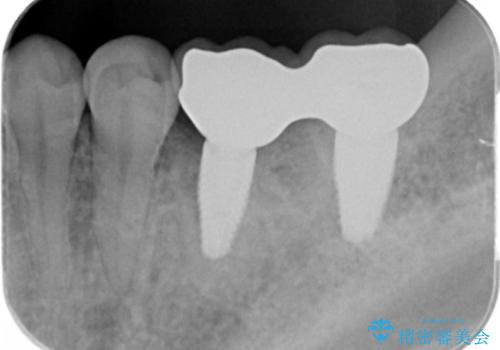

合計3本の奥歯を抜歯したところに、インプラント治療を行っています。

また、左上奥歯の根の治療および右下の虫歯治療も併せて行っています。